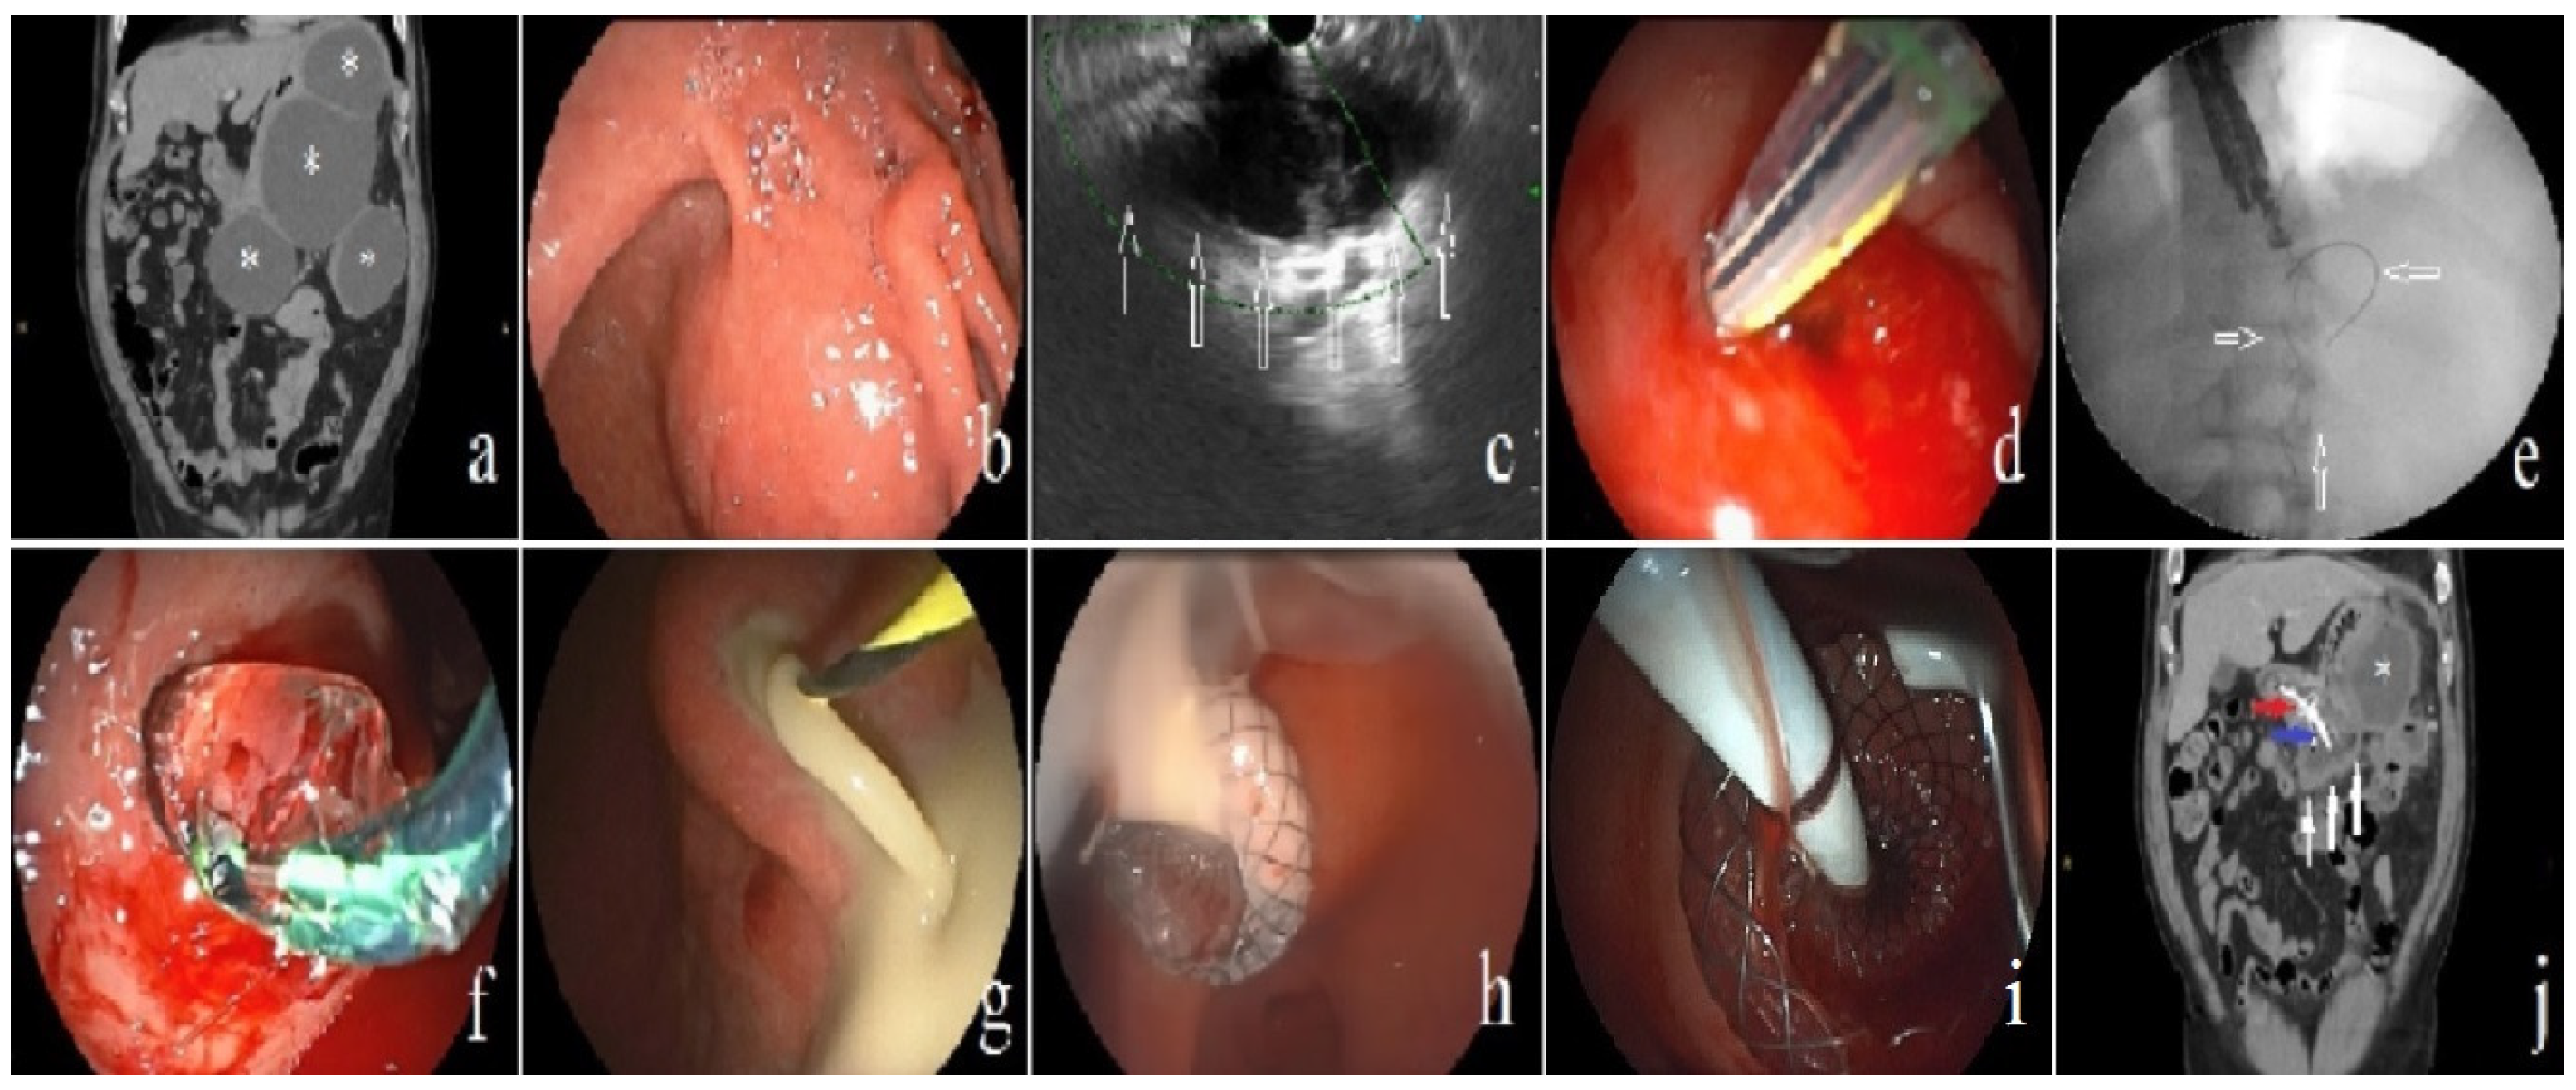

| Direct endoscopic necrosectomy needed | 7 (63.6) |

| Additional percutaneous intervention | 6 (54.5) |

| Clinical success with a combination of percutaneous and endoscopic management | 6 (54.5) |

| Largest dimension of WON cavity (mm) | 200 (130–238) |

| Single WON cavity | 2 (33.3) |

| Multiple WON cavities | 4 (66.6) |